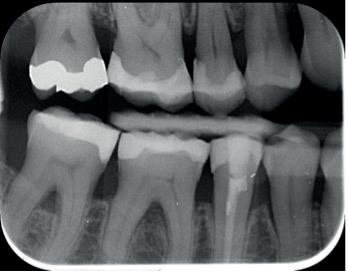

Een 62-jarige man hield in de nazorgfase een pocket van 8 mm met bloeding na sonderen mesiaal van de 36 ondanks 3-maandelijkse recall (afbeelding 2.1 en 2.3). De mondhygiëne was matig en plaque was aanwezig. Chirurgie werd geadviseerd, maar de pa-

tiënt wees dit af. Ook hier werd de pocket behandeld onder anaesthesie. De natriumhypochloriet/aminozuur-gel werd viermaal aangebracht, telkens gevolgd door ultrasone en handinstrumentatie. Tot slot werd cross-linked hyaluronzuur ingebracht. De mondhygiëne werd bijgestuurd en meneer werd gemotiveerd dagelijks interdentale ragers te gebruiken naast het poetsen.

Na zes maanden was de pocketdiepte teruggebracht tot 3 mm en was er geen bloeding na sonderen (afbeelding 2.2 en 2.4).